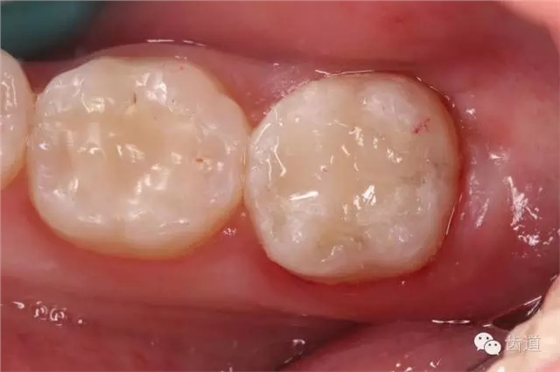

10. 術(shù)后即刻口內(nèi)照片

檢查:術(shù)后半年回訪,37牙體及合面嵌體未見缺損及裂紋,邊緣密合,未探及繼發(fā)齲,探痛-,叩痛-,松動(dòng)-,冷水刺激痛-,未探及牙周袋及附著喪失,牙齦無紅腫,X線片檢查示根尖周膜連續(xù)性恢復(fù),根尖周透射影消失。